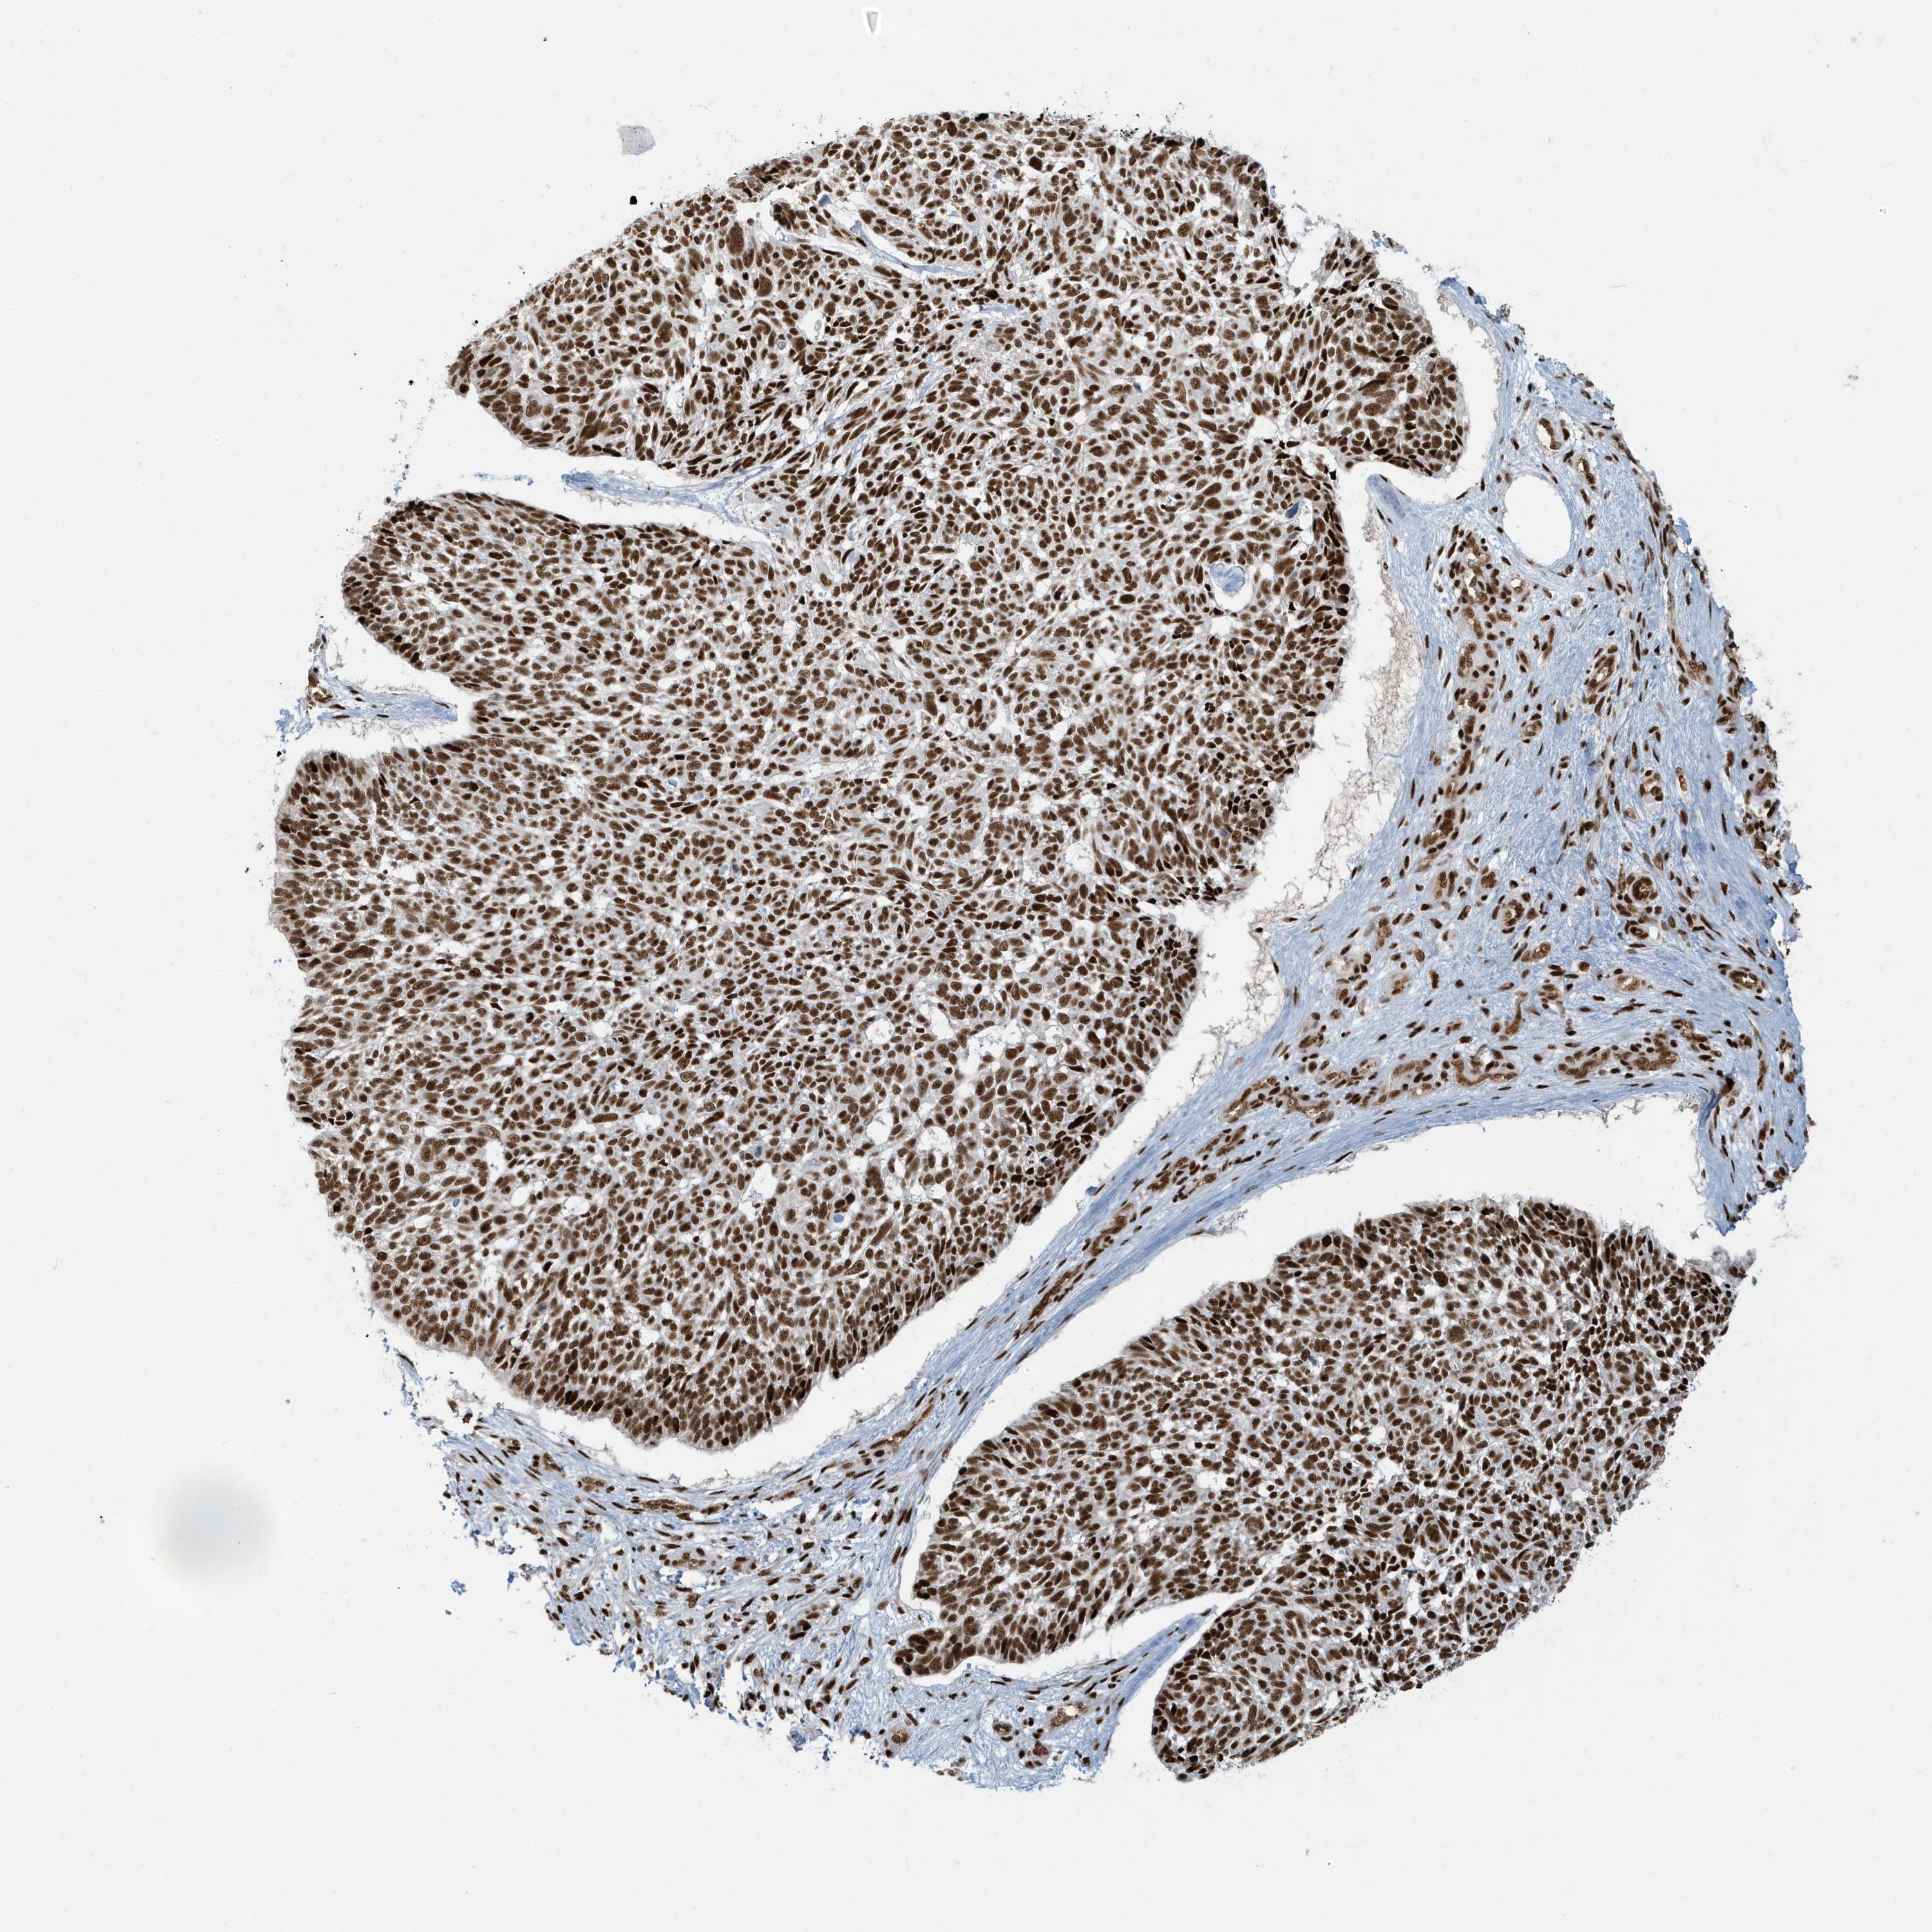

Basal cell and squamous cell cancer

SKIN CANCER - Protein expressioni

A mouse-over function shows sample information and annotation data. Click on an image to view it in a full screen mode. Samples can be filtered based on level of antibody staining by selecting one or several of the following categories: high, medium, low and not detected. The assay and annotation is described here.

Antibody stainingi

Antibody staining in the annotated cell types in the current human tissue is reported as not detected, low, medium, or high, based on conventional immunohistochemistry profiling in selected tissues. This score is based on the combination of the staining intensity and fraction of stained cells.

Each image is clickable and will lead to virtual microscopy that enables deeper exploration of all samples and also displays staining intensity scores, fraction scores and subcellular localization as well as patient and tissue information for each sample.

Antibody HPA030762

Staining

High

Intensity

Strong

Quantity

>75%

Location

Nuclear

Basal cell carcinoma